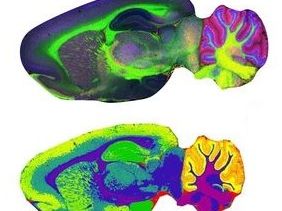

Mathematik und medizinische Bilder

Wir sind längst im Zeitalter der digitalen Medizin angekommen. Medizinische Daten und Bilder, welche mit modernen physikalischen Methoden erfasst werden, haben einen so hohen Informationsgehalt, dass mathematische Modellierung und Simulation einen erheblichen Mehrwert beitragen. Von der Optimierung der Erfassung, der Aufbereitung der Daten, der Simulation der physiologischen Prozesse, bis zur Optimierung der Therapie, ist die angewandte Mathematik ein Grundpfeiler der modernen Medizin. Hier ist die Arbeit eines Mathematikers nah an den Schnittstellen zu anderen Fachbereichen, oft zu Physik, Medizin, Informatik und Biologie.

Dr. Cristoffer Cordes arbeitet am Fraunhofer MEVIS als Forscher. Er hat an der Universität Bremen Mathematik studiert und seinen Master von der Clemson University (USA) verliehen bekommen. Danach hat er an der Universität Bremen in Physik promoviert. Sein Hauptfokus ist die MRT-Simulation und die abstrakte MRT-Sequenzentwicklung.

Mathematik in den Life Sciences

Die Technologie der bildgebenden Massenspektrometrie ermöglicht die örtliche Lokalisierung und Quantifizierung von Molekülen, wie beispielsweise Proteinen, Peptiden oder Wirkstoffen. Anwendungen findet die bildgebende Massenspektrometrie beispielsweise in der Pharmakologie zur Entwicklung neuer Medikamente und Wirkstoffe, in der medizinischen Forschung zur Erforschung neuer Therapien, in der Pathologie zur Detektion neuer krankheits-charakterisierender Biomarker und in den Materialwissenschaften zur Optimierung neuer Werkstoffe. Die riesigen Datenmengen der bildgebende Massenspektrometrie zu visualisieren, zu analysieren und zu interpretieren ist eine Herausforderung, die man mit Hilfe mathematischer Verfahren bewältigen kann.